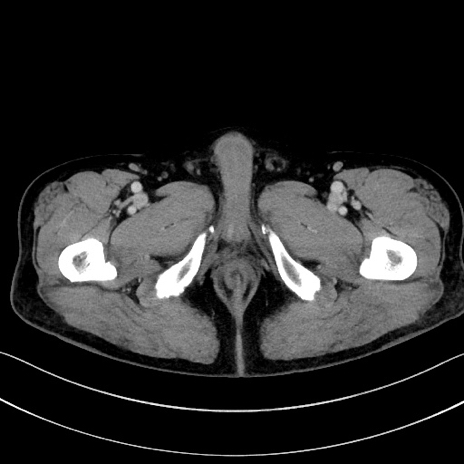

症例15(横断像)

【症例】70歳代男性

【主訴】腹痛

【現病歴】今朝から腹痛あり。全体的に痛い。特に左上の方。排ガスが今日はない。冷や汗が出る。

【既往歴】直腸癌術後

【身体所見】左側腹部〜上腹部に圧痛あり。腹膜刺激症状明らかなではない。軽度反跳痛。左下腹部に術後瘢痕あり。

【データ】WBC 7700、CRP 0.02